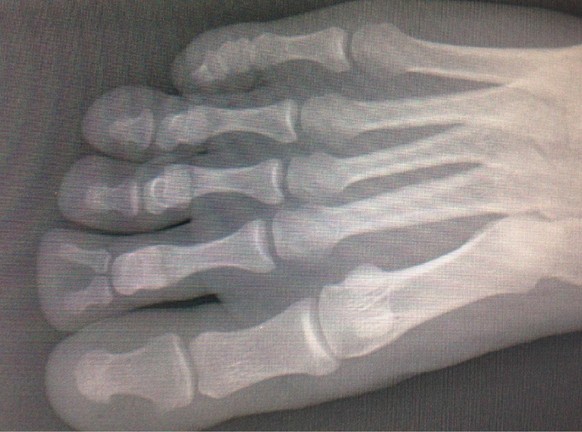

Vous voyez ce qui est atypique ici?

Tada!